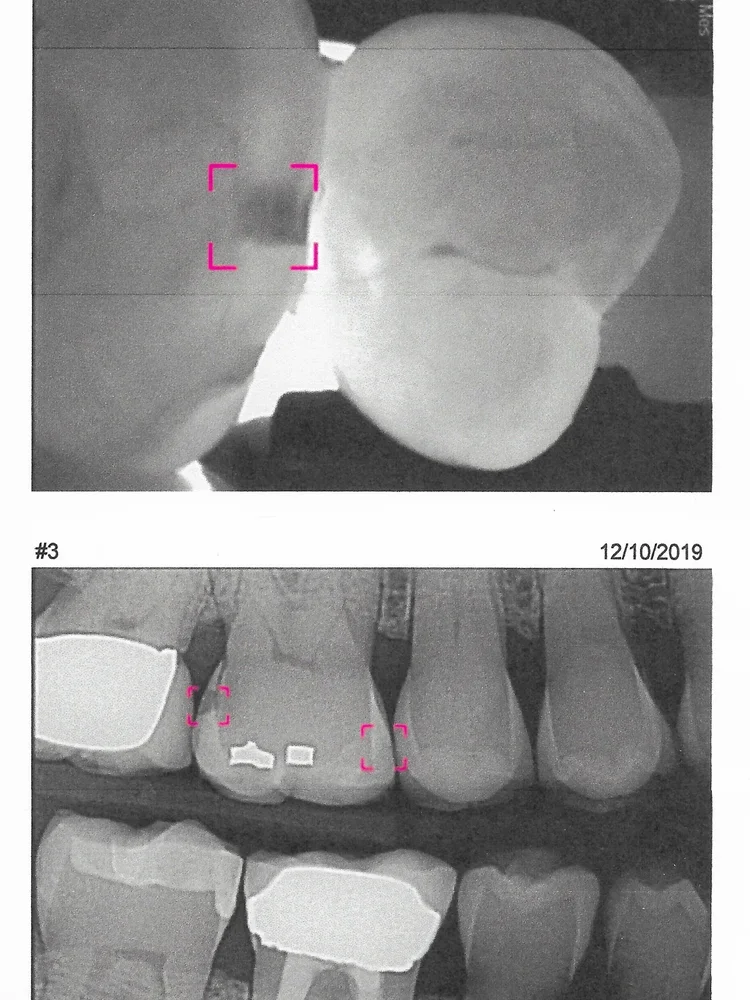

CARIVU TECHNOLOGY

The image on top (to the left) was taken with the newest of technologies, CariVu, to assist in diagnosing the existence of decay or fractures in teeth at the earliest of stages. Having this diagnostic tool allows for the most conservative of treatment and early detection. The image was attained by transmitting an infrared light (with no radiation) through the tooth. This trans-illumination captures an image that is generated to our dental software program. The dark shadow highlighted by the pink box in this top image indicates decay that was undetectable in a traditional two dimensional X-ray (right pink box shown beneath it). The traditional digital X-ray does not reveal this same decayed area on the right side of the tooth (the pink box on the right side of the middle picture). The two dimensional dental X-ray only reveals a decayed area on the left side of the tooth (the dark shadow inside the pink box on the left side of the middle picture). In this case the area inside that left pink box was correctly treated by the dentist. However without being able to visualize any condition inside right pink box (without the aid of CariVu) the “invisible” decay on the right was left untreated. As with any medical or dental condition, the earlier a condition is diagnosed the more conservative and comprehensive the treatment can be.

As you can see from the photograph, the CariVu Detection device is a streamlined infrared imaging system that captures its image by gripping the tooth in question with soft rubber sleeves. This very effective diagnostic aid only takes seconds to use but helps us to determine whether or not observations found through clinical examination and X-rays actually require treatment.